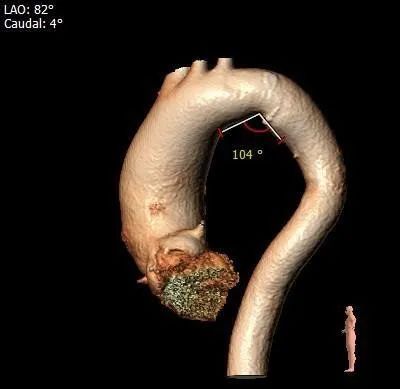

主动脉弓测量:

主动脉弓部宽度、角度可

•主动脉瓣水平夹角约60°,横位心,主动脉弓宽度角度可,弓顶部散在附壁钙化